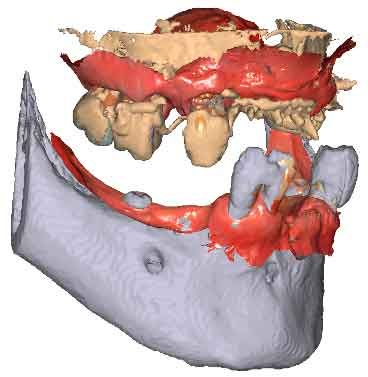

3D models - Bite scan from intra-oral scanner

Step 2 – CBCT acquisition

When traditional IOS scans lack necessary references, Cone Beam Computed Tomography (CBCT) data serves as a possible alternative. By utilizing CBCT scans, clinicians can establish accurate reference positions for treatment planning.

To be able to use CBCT data as initial models, we need to transform the DICOM file into an STL file.

By importing patient DICOM files instead of the IOS scans, clinicians can register jaw motion, facilitating precise treatment planning.